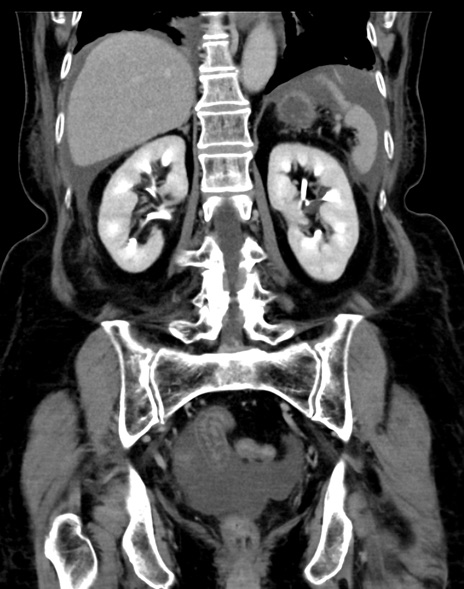

(横断像)1日半後